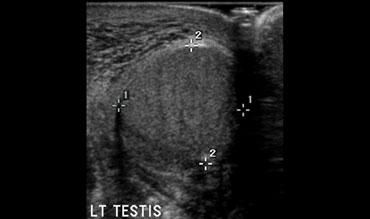

Cách để nhận biết sự khác biệt về độ hồi âm là chụp ảnh cắt ngang của cả hai tinh hoàn.

Các hình ảnh bên trái cho thấy bên bị ảnh hưởng có kích thước lớn hơn và độ hồi âm cao hơn.

Tinh hoàn này có thể không còn khả năng bảo tồn.

Tinh hoàn có thể có độ hồi âm cao hơn hoặc thấp hơn, điều đó không quan trọng, miễn là có sự khác biệt thì tiên lượng sẽ xấu.